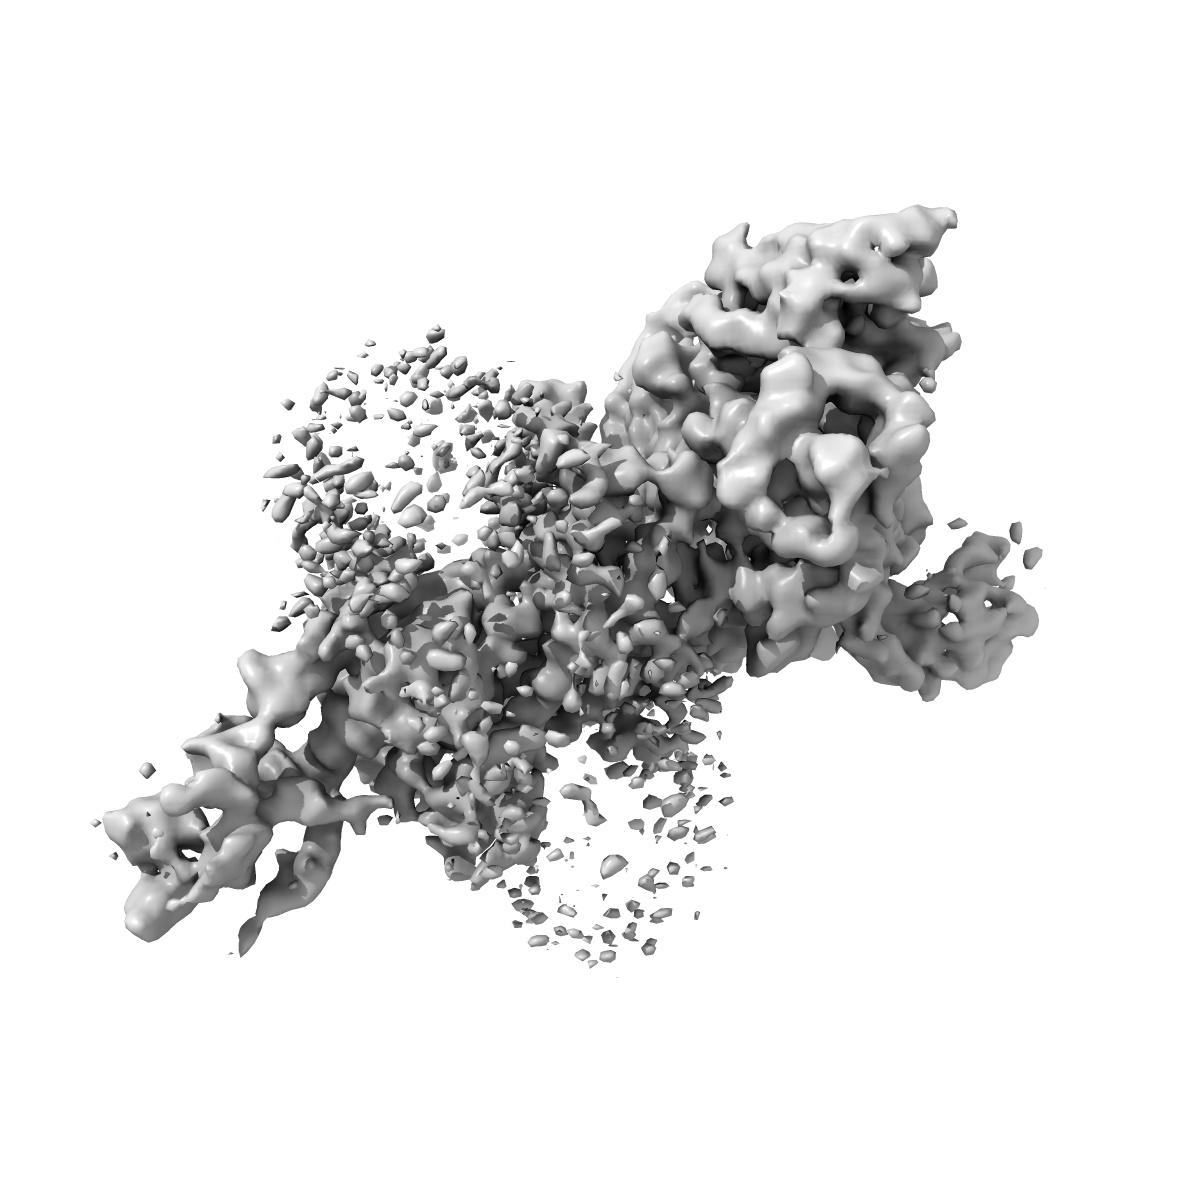

Cryo-EM structure of parathyroid hormone receptor type 1 in complex with a long-acting parathyroid hormone analog and G protein

Single-particle4.0 Å

Sample: Cryo-EM structure of parathyroid hormone receptor type 1 in complex with a long-acting parathyroid hormone analog and G protein

Fitted models: 6nbi